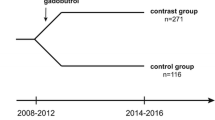

A total of 90 patients received at least two examinations with T1 mapping during the study period. Twenty-eight patients were excluded because of a history of radiotherapy, eight due to prior administration of another contrast agent and two because of extensive pathology (Fig. 1). No patient was excluded due to renal insufficiency. Thus, 52 patients (median age 11 years, IQR 6–15, 26 female) were included in the study.